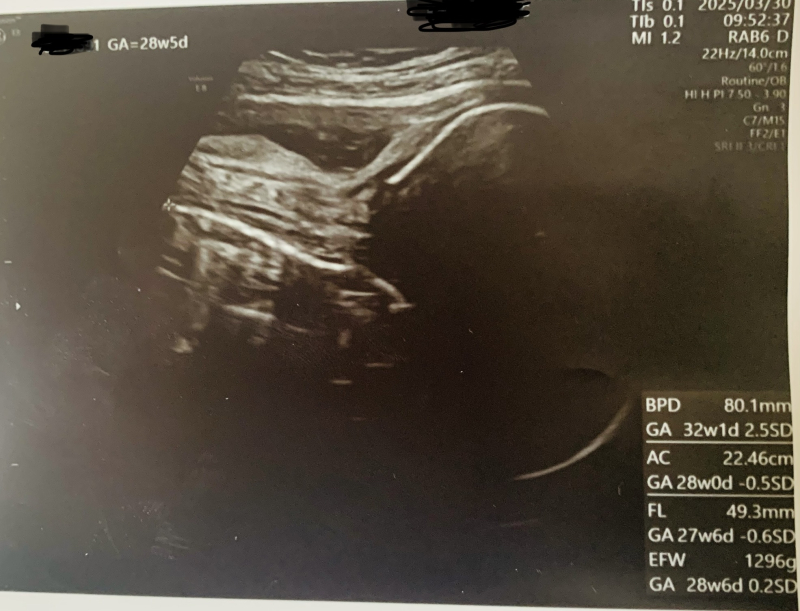

現在28週5日です。 直近で産婦人科にて診察を受けた際に、エコー写真から頭部が現在の週数と比較し3週間程大きいことがわかりました。

何気なく写真に書かれていたBPDについて検索していると「胎児の頭部が平均より大きいとダウン症の傾向にある」と出てきました。

太ももの骨の長さが週数に比べ短いことも気になります。

足の骨の短さも不安があるようですが、お腹周りなどからみても、平均的な長さな感じがします。

確かに全体的なバランスから見ていきますと、やや頭部の大きさが大きめです。

ですが、計測はミリ単位でも、推定週数が変わって計算されますので、現段階一点だけで頭部拡大と診断することはありませんし、異常を強く疑いません。